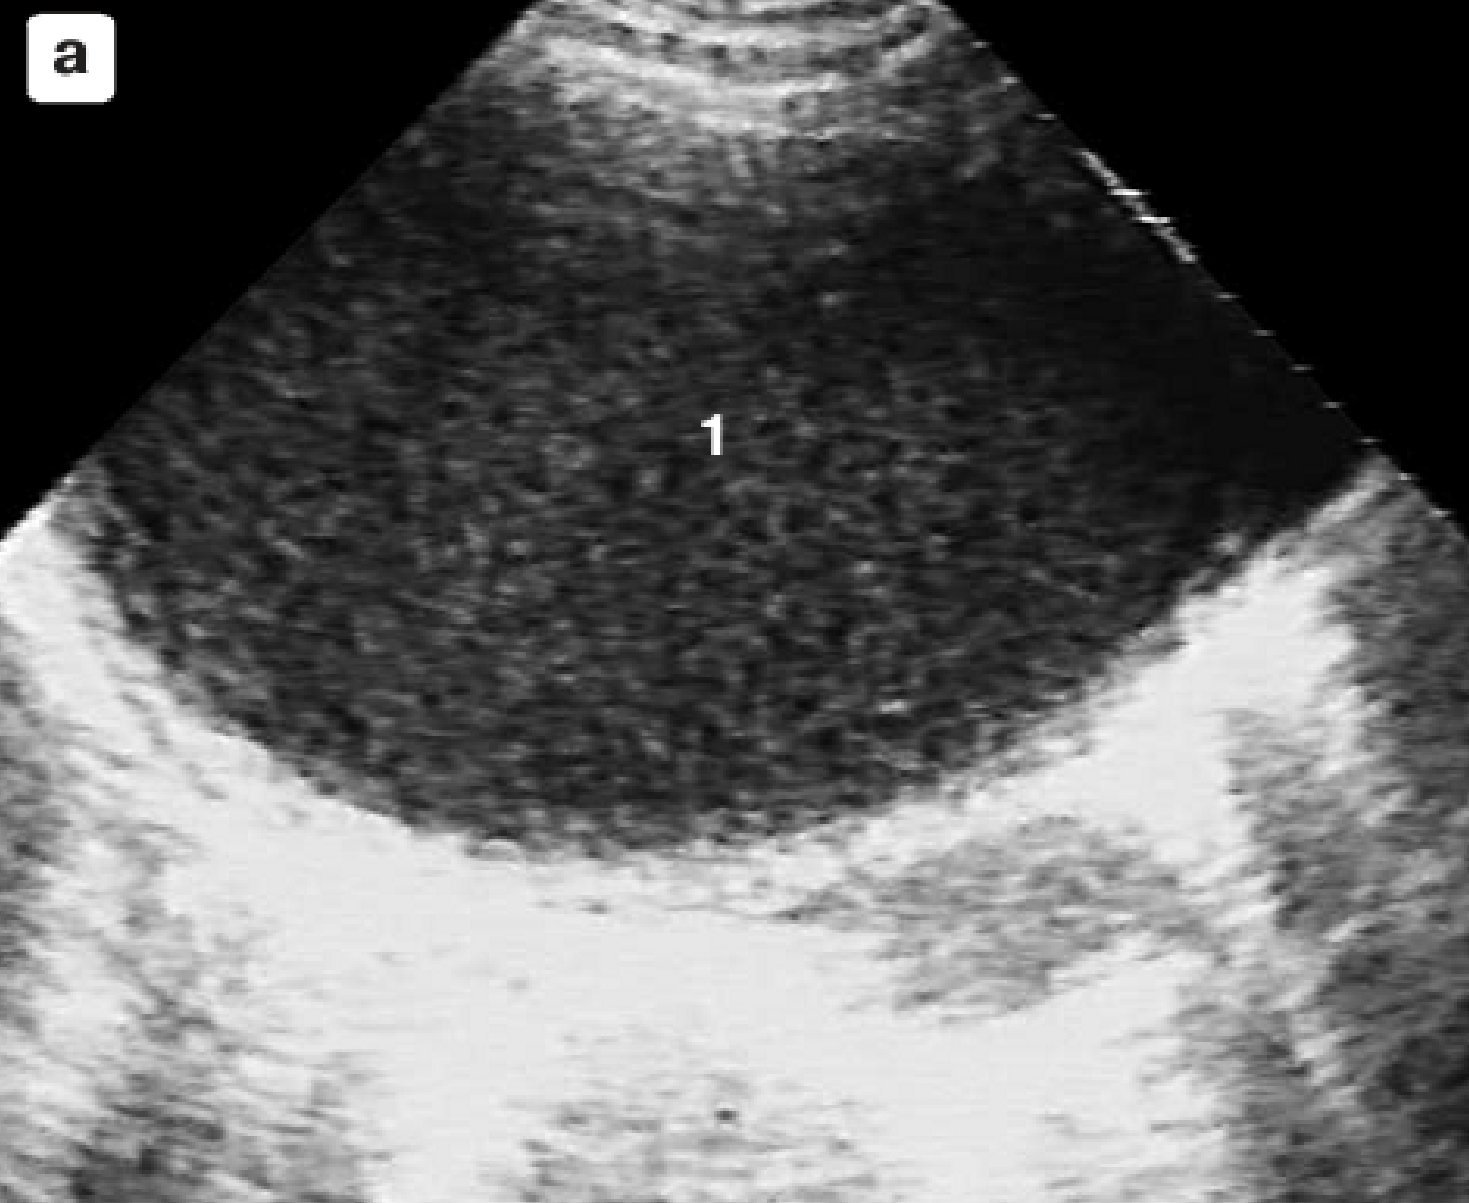

Прогрессирование

деструктивного

процесса

с отсутствием признаков формирования пиогенной капсулы (а);

сообщение полости гнойника с одним из бронхов (б).